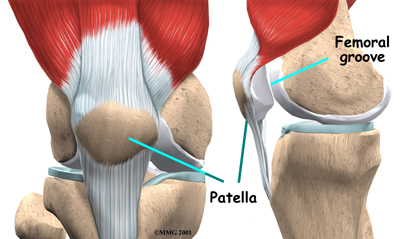

The underside of the patella is covered with articular cartilage, the smooth, slippery covering found on joint surfaces. This covering helps the patella glide (or track) in a special groove made by the thighbone, or femur. This groove is called the femoral groove.

Two muscles of the thigh attach to the patella and help control its position in the femoral groove as the leg straightens. These muscles are the vastus medialis obliquus (VMO) and the vastus lateralis (VL). The VMO runs along the inside of the thigh, and the VL lies along the outside of the thigh. If the timing between these two muscles is off, the patella may be pulled off track.

One of the more common causes of knee pain is a problem in the way the patella tracks within the femoral groove as the knee moves. The quadriceps muscle helps control the patella so it stays within this groove. If part of the quadriceps is weak for any reason, a muscle imbalance can occur. When this happens, the pull of the quadriceps muscle may cause the patella to pull more to one side than the other. This in turn causes more pressure on the articular cartilage on one side than the other. In time, this pressure can damage the articular cartilage.

One of the more common causes of knee pain is a problem in the way the patella tracks within the femoral groove as the knee moves. The quadriceps muscle helps control the patella so it stays within this groove. If part of the quadriceps is weak for any reason, a muscle imbalance can occur. When this happens, the pull of the quadriceps muscle may cause the patella to pull more to one side than the other. This in turn causes more pressure on the articular cartilage on one side than the other. In time, this pressure can damage the articular cartilage.